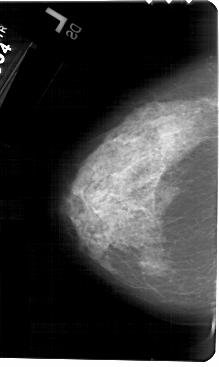

A_1511_1.RIGHT_MLO

RIGHT_MLO LINES 5491 PIXELS_PER_LINE 3316 BITS_PER_PIXEL 12 RESOLUTION 43.5 OVERLAY